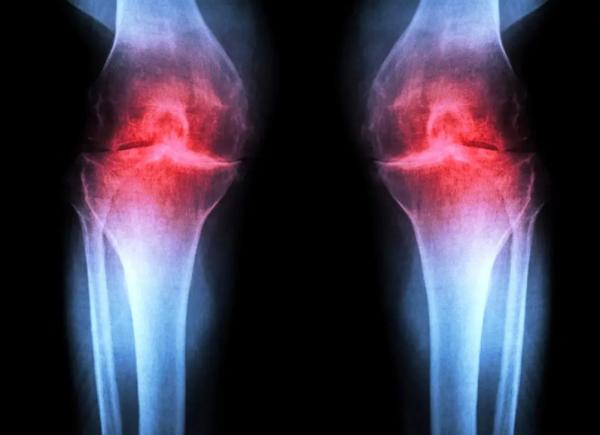

سه نوع اصلی غضروف در بدن انسان وجود دارد. غضروف الاستیک نرم و انعطافپذیر است و ساختارهایی مانند لالهی گوش را تشکیل میدهد. غضروف فیبری (فیبروغضروف) متراکم و سخت است و ضربه را در نواحی مانند بین مهرههای ستون فقرات جذب میکند. نوع سوم، غضروف هیالین، صاف و براق است و سطحی کماصطکاک برای روانسازی و انعطافپذیری مفاصل مانند مچ پا، لگن، شانه و بخشهایی از زانو فراهم میکند. غضروف هیالین که به آن غضروف مفصلی هم گفته میشود، بیشترین درگیری را در آرتروز دارد.

آرتروز زمانی رخ میدهد که مفصل بر اثر پیری، آسیب یا چاقی تحت فشار قرار گیرد. کندروسیتها شروع به آزادسازی مولکولهای پیشالتهابی و تجزیهی کلاژن (پروتئین ساختاری اصلی غضروف) میکنند. با از دست رفتن کلاژن، غضروف نازک و نرم میشود و التهاب همراه، تورم و درد مفصل را (که از ویژگیهای بارز بیماری است) ایجاد میکند. در شرایط عادی، غضروف مفصلی بهندرت بازسازی میشود. اگرچه برخی جمعیتهای فرضی از سلولهای بنیادی یا پیشسازِ قادر به تولید غضروف در استخوان شناسایی شدهاند، تلاشها برای یافتن جمعیتهای مشابه در غضروف مفصلی موفقیتآمیز نبوده است.